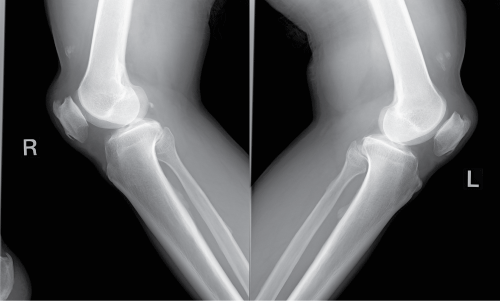

A 72-year-old man injured both knees after he slipped off a step. He was unable to stand up afterward and went to a clinic where his injury was diagnosed radiographically as contusions of both knees accompanied by muscle weakness. Five days later, clinical examination in our hospital showed a supra-patellar gap (Figure 1), moderate hemarthrosis of both knees, and failure of active knee extension. Based on this, the patient was diagnosed with bilateral rupture of the quadriceps tendons. Magnetic resonance imaging (MRI) confirmed the diagnosis, showing the quadriceps tendon rupture at the osteotendinous junction (Figure 2). Radiographs of his knees revealed the delle in the suprapatellar soft tissue, low-riding patella [3] and an avulsion fragment on the patella (Figure 3). The patellar heights of his right and left knees were 0.89 and 0.68, respectively, using the Insall-Saivati method. He did not have concomitant diseases.

Figure 3: Radiographs on lateral view of Case 1. Patella baja and avulsion bony fragment.

A 69-year-old man fell down on a small hill when he was walking down a mountain. He complained of painful knees and was unable to extend his knees and stand up afterward. He went to a hospital and was diagnosed radiographically with muscle weakness and contusions on both knees. Two days following the fall, bilateral ruptures of the quadriceps tendons were diagnosed by clinical examination in our hospital. The diagnosis was based on the supra-patellar gap, moderate hemarthrosis of both knees, and failure of active knee extension. Magnetic resonance imaging (MRI) confirmed the diagnosis showing the quadriceps tendon rupture at the osteotendinous junction. Radiographs showed patellar baja and an avulsion of small bony fragments above the patella. The patellar height was 0.88 on the right knee and 0.87 on the left knee using the Insall-Salvati method. No systemic concomitant diseases were diagnosed.

The patients reported here were misdiagnosed initially, in part because diagnosis was made using only radiographs. Radiographs can provide evidence of quadriceps tendon rupture by showing an obliteration of the quadriceps tendon shadow, a patella baja (low-riding patella), and a suprapatellar soft tissue mass representing retraction of torn tendons, and an avulsion of small bony fragments from the pole of the patella. However, radiographs are rarely sufficient to make the correct diagnosis [13]. It is reported that only 33% of quadriceps tendon ruptures were diagnosed correctly with radiography alone [13]. Bilateral quadriceps tendon rupture may be interpreted as a neurological deficit due to muscle weakness [14]. Both patients in this series were misdiagnosed as having muscle weakness and contusion with effusion and swelling. However, an adequate physical examination together with radiographic or MRI images can prevent misdiagnosis.